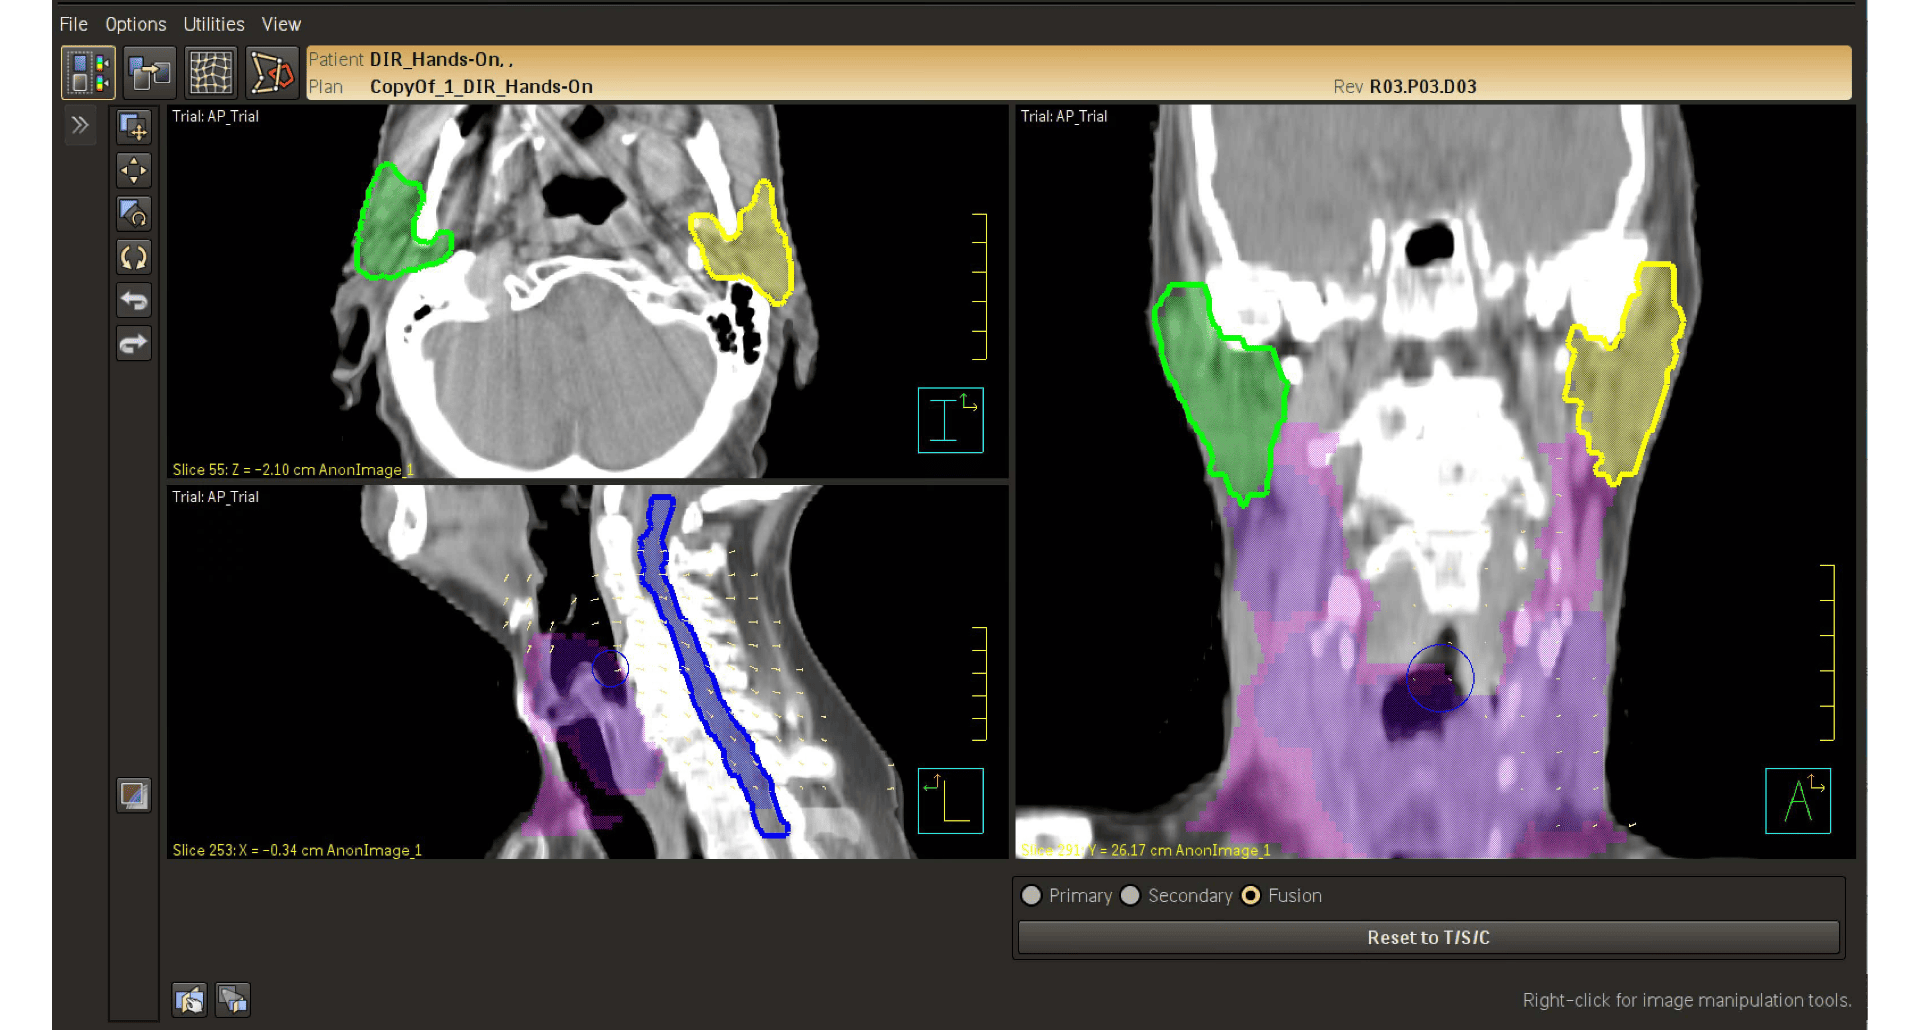

Удобные средства оценки позволяют параллельно сравнивать изображения и планы пациента, визуализируя изменения в его организме на основе данных первоначальных контуров. На гистограммах «доза — объем» можно увидеть, каким образом будет распределена доза облучения с учетом анатомических изменений. Необходимость в создании новых планов может быть оценена с одного взгляда.